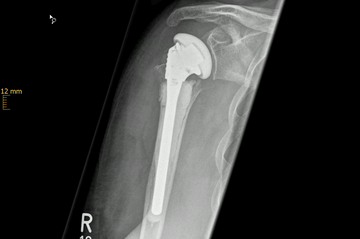

Oberarmfrakturen

Oberarmfrakturen sind häufige Frakturen der älteren Menschen. Mit der Radiusfraktur (Handgelenk), den hüftgelenknahen Frakturen und den Wirbelkörperfakturen gehören sie zu den häufigsten osteoporotischen Extremitätenfrakturen. Durch ein Sturzgeschehen mit Anprall auf den Ellenbogen oder das Abfangen des Sturzes auf die ausgestreckte Hand entsteht eine axiale Krafteinwirkung auf die Schulter, die zur Fraktur führt (Niedrigenergietrauma). Bei jüngeren Patienten sind es häufig Stürze im Rahmen von Sport- oder Verkehrsunfällen (Hochenergietrauma).

Der große Kopf des Schultergelenkes ist direkt an seinem Übergang zum Schaft des Oberarmes besonders frakturgefährdet. An dieser Stelle kommt es häufig zu Brüchen (subkapitale Humerus-Fraktur).

Verschobene Frakturen und solche mit deutlicher Gelenkstufenbildung müssen in der Regel operiert werden. Die Notwendigkeit nimmt dann zu, wenn durch die Fraktur die Oberarmkopfdurchblutung gefährdet ist oder eine starke Verschiebung der Frakturfragmente keine akzeptable Funktion des Schultergelenkes erwarten lässt. Der Vorteil der operativen Behandlung (Osteosynthese) ist neben der möglichst anatomischen Reposition und Stabilisation die frühfunktionelle Nachbehandlung.

In wenigen Fällen besteht auf Grund der Frakturform die Notwendigkeit, das Schultergelenk sofort durch eine Endoprothese zu ersetzen.